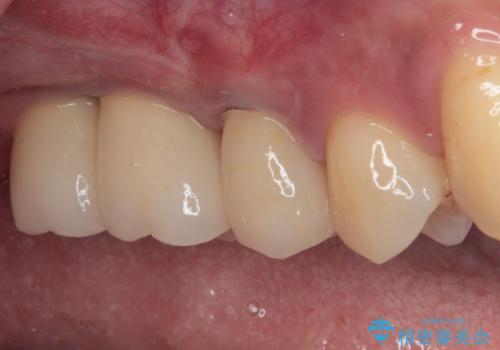

前歯部については抜歯が必要な歯を抜歯し、インプラントやブリッジなどにより補綴治療を行うこととしました。

臼歯部は今後抜歯が必要となった際に、インプラントにより咬合を構築していくこととしました。今回の治療においても、今後の臼歯部の治療に対応できるよう治療計画を立案しています。